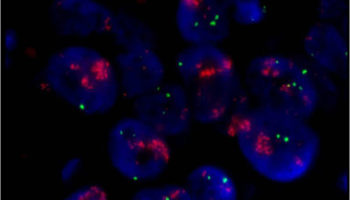

A laboratory test that can be used to look for HER-2/neu gene amplification in breast cancers. This test uses a probe molecule that has an attached fluorescent tag; when the HER-2/neu gene is present, the probe binds to the gene and shines brightly. The number of genes can be counted using a special fluorescent light microscope.